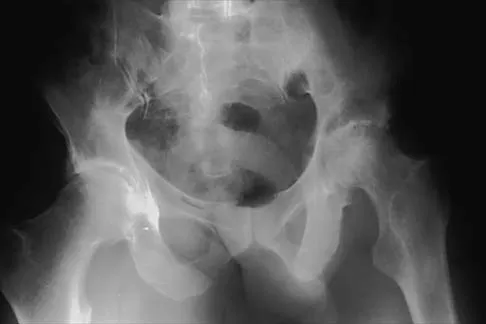

Figure 36 shows the radiograph of a patient who has hip pain and is unable to ambulate. What is the most appropriate management for this patient?

The patient has a periprosthetic fracture of the greater trochanter - Vancouver A. The reason for the fracture of the greater trochanter is the extensive periarticular osteolysis that has occurred as a result of polyethylene wear. The latter is demonstrated by eccentric seating of the large femoral head in the acetabulum. The most appropriate management is to reverse the osteolysis process, which involves exchange of the acetabular liner with or without revision of the other components depending on their fixation and position. The greater trochanter can also be fixed during revision surgery. Duncan CP, Masri BA: Fractures of the femur after hip replacement. Instr Course Lect 1995;44:293-304.